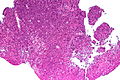

Medulloblastoma

- Tumour of cerebellum - key feature.

- Morphologically identical supratentorial tumours are called primitive neuroectodermal tumour (PNET).

Primitive neuroectodermal tumour